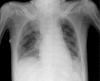

Fig. 1

Fig. 1. Chest X-ray findings. Partial atelectasis in the lower lobes of both lungs is shown.